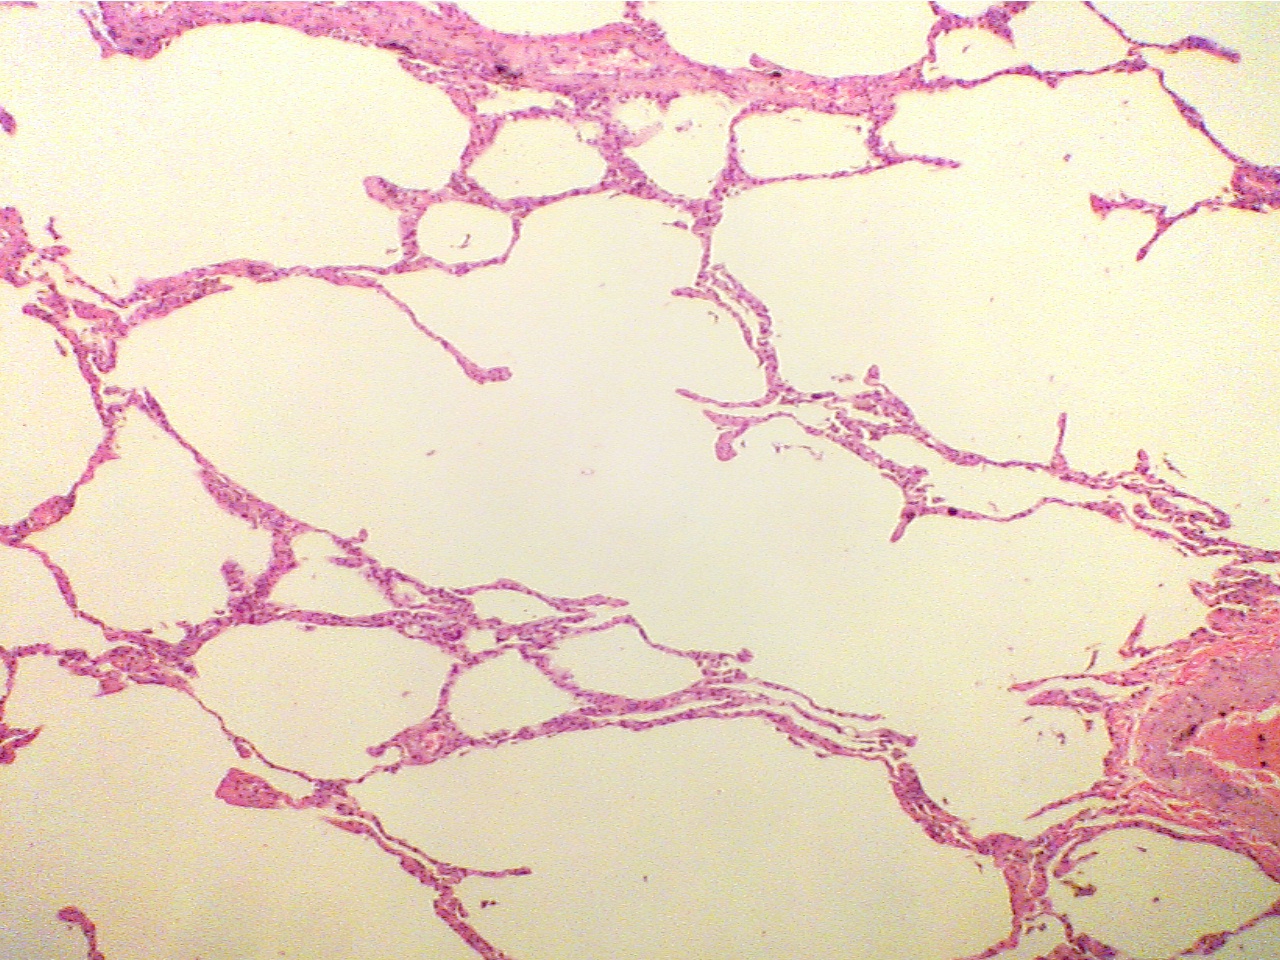

Pulmonary emphysema

Note that the alveoli (air spaces) in this slide are much larger than in the slide of normal lung. The functional efficiency of this lung is much reduced as compared to normal.

Emphysema (40X2.0)                                                                      Normal lung (40X2.0)

Destruction of tissue leaves little surface area, few                Much normal tissue creates large surface area

capillaries, and large air spaces. Large vessel at lower         with many capillaries, many small air spaces. Large

right                                                                                               vessel at extreme left, large airway at lower right

Emphysema (100X2.0)

capillaries, and large air spaces                                                  with many capillaries, which are filled with